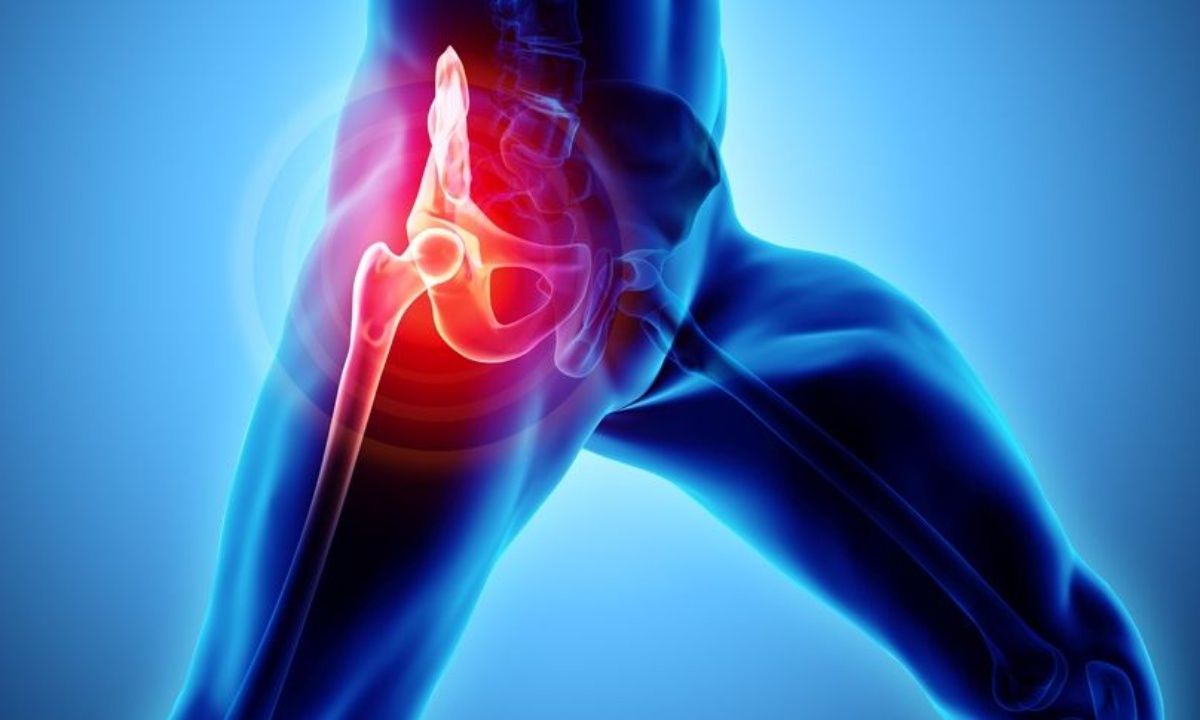

Οστεοαρθρίτιδα ισχίου: Οι βασικοί παράγοντες κινδύνου

Η άρθρωση του ισχίου είναι αυτή που συνδέει τη λεκάνη με το κάτω άκρο και στηρίζει το βάρος του κορμού.

Είναι η άρθρωση εκείνη που συμμετέχει στη βάδιση, στη στροφή και την κάμψη του κάτω άκρου με αποτέλεσμα να δέχεται μεγάλα φορτία, κατάσταση που την καθιστά επιρρεπή σε τραυματισμούς και εκφυλιστικές νόσους όπως είναι η οστεοαρθρίτιδα.